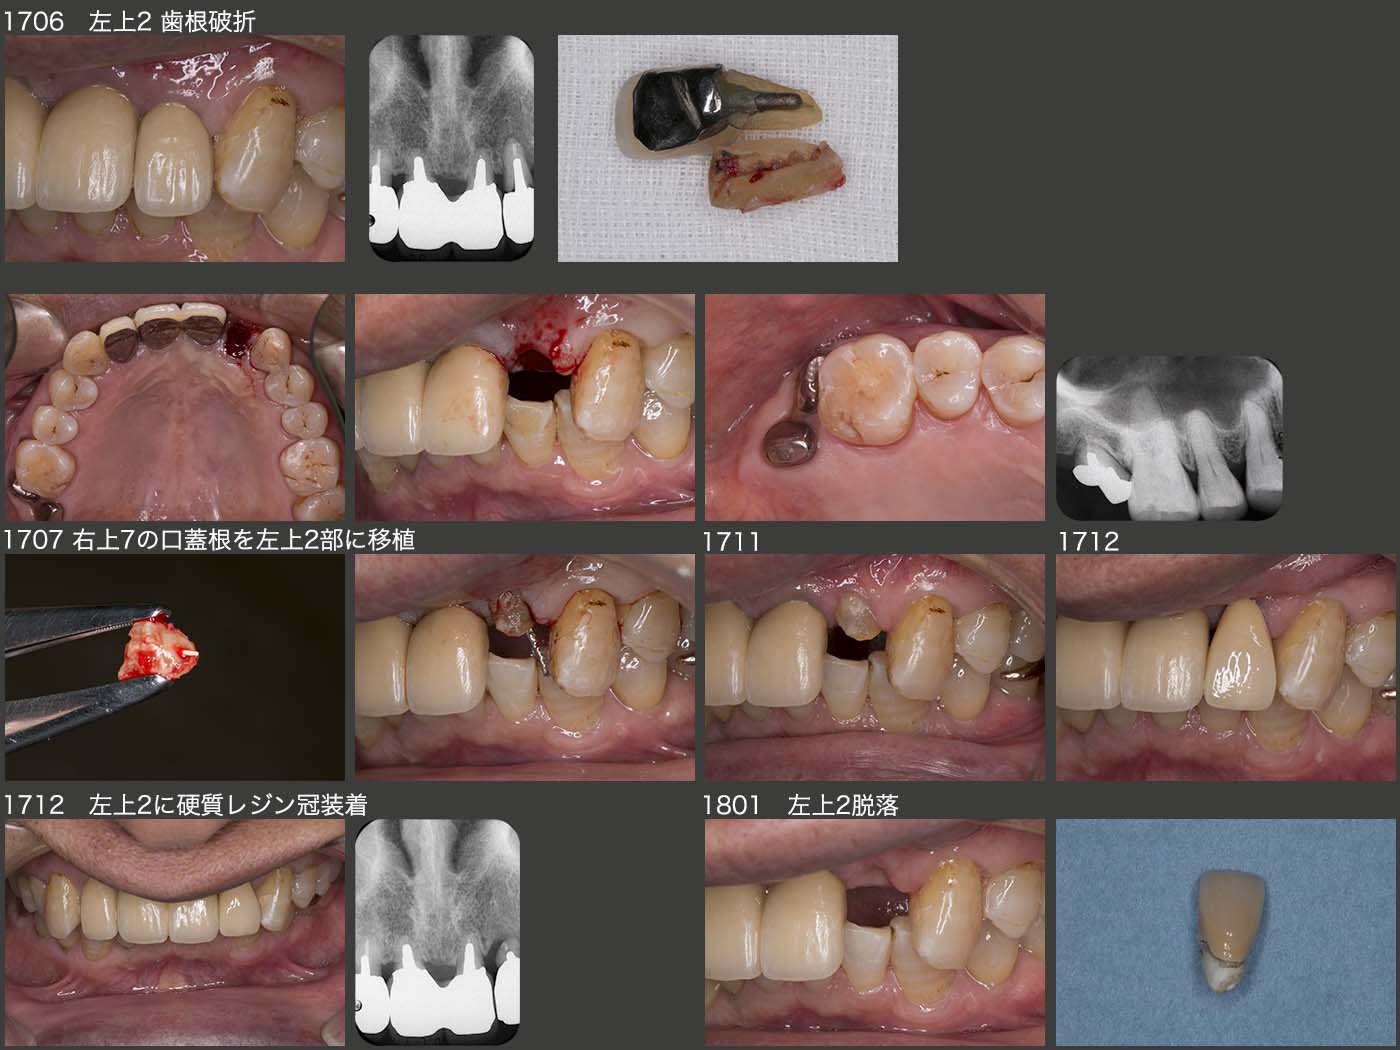

2017年6月,恐れていた事態が生じた.すなわち,左上2の歯根破折である.上顎前歯で嚙み切ってはいけないと口が酸っぱくなるくらい注意してきたが,焼き鳥を食べて万事休すといったところである.上顎中切歯は連結固定してあり,もう一度ブリッジの支台歯にするためにメタルボンド冠を作り直す気にはどうしてもならなかった.

そこで目を付けたのが,とりあえず保存しておいた右上7の残根である.17年7月,口蓋根を抜歯し,左上2部に移植した.歯根は著しく短いが,移植後の動揺は思っていたより少なかったので,17年12月に硬質レジン前装冠を装着した.

しかし,悲しいことに18年1月,今度はお握りを食べて脱落してしまった.患者曰わく,お握りの中に肉の塊があり,それがあたり脱落したとのことである.1ヵ月も保たなかった.いくらここで嚙んではいけないと申し伝えても,お握りで脱落するような冠を装着した私に責任があり,大いに反省している.